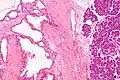

| Micrograph showing a pancreatic serous cystadenoma. H&E stain. | |